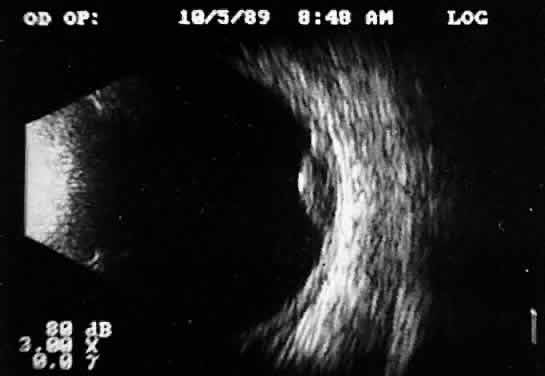

Recent improvements in computer technology and digital B-scan devices have permitted the development of tomographic (3D) static displays. The new devices, often called 3D ultrasound instruments, increase understanding of complex topographic information (Fig. 18). Sophisticated software permits measurements of captured images (linear, area, and volume) as well as surface renderings18,19 (Figs. 19 and 20). Kinetic (real-time) information is not yet available in 3D and continues to be obtained during kinetic B-scan examinations performed before 3D image capture.

Fig. 20. 3D tomographic ultrasonogram: linear measurement of a melanoma height derived from tomographic B-scan.